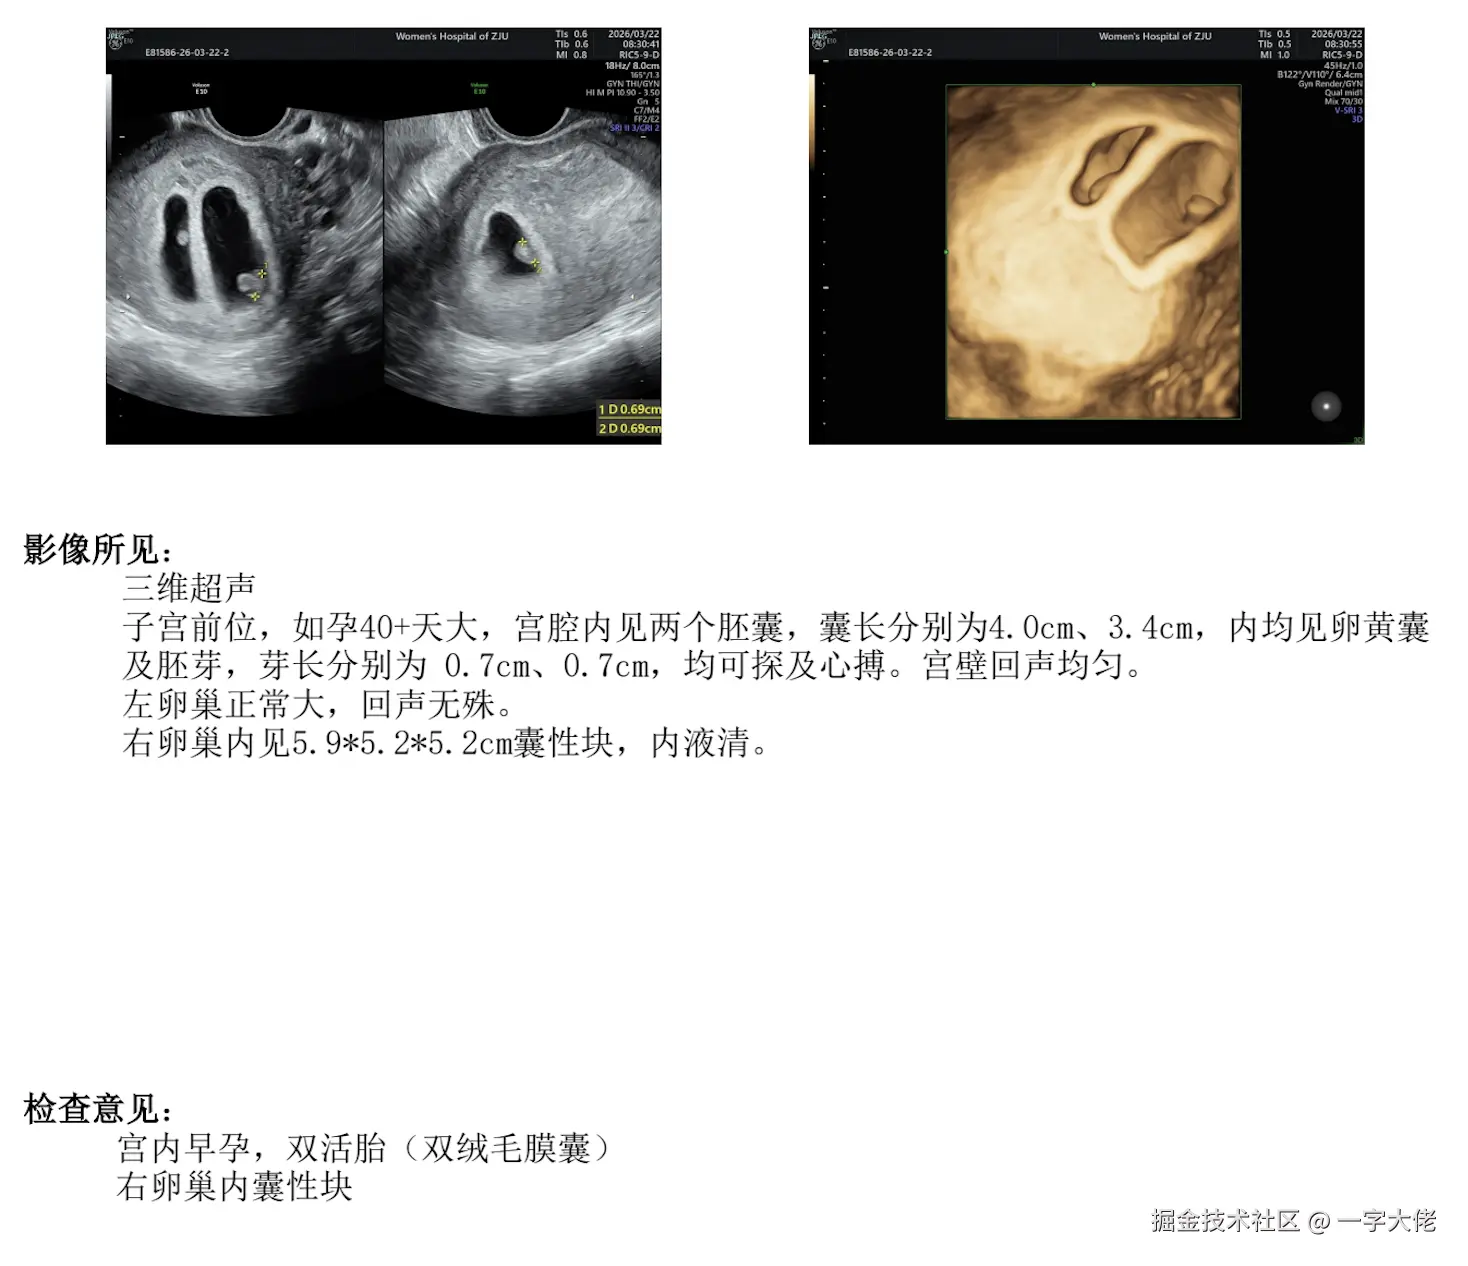

又发现媳妇儿一个逆天技能,这么多年我一直都被蒙在鼓里啊,看来对媳妇儿的开发进度要加快一点了